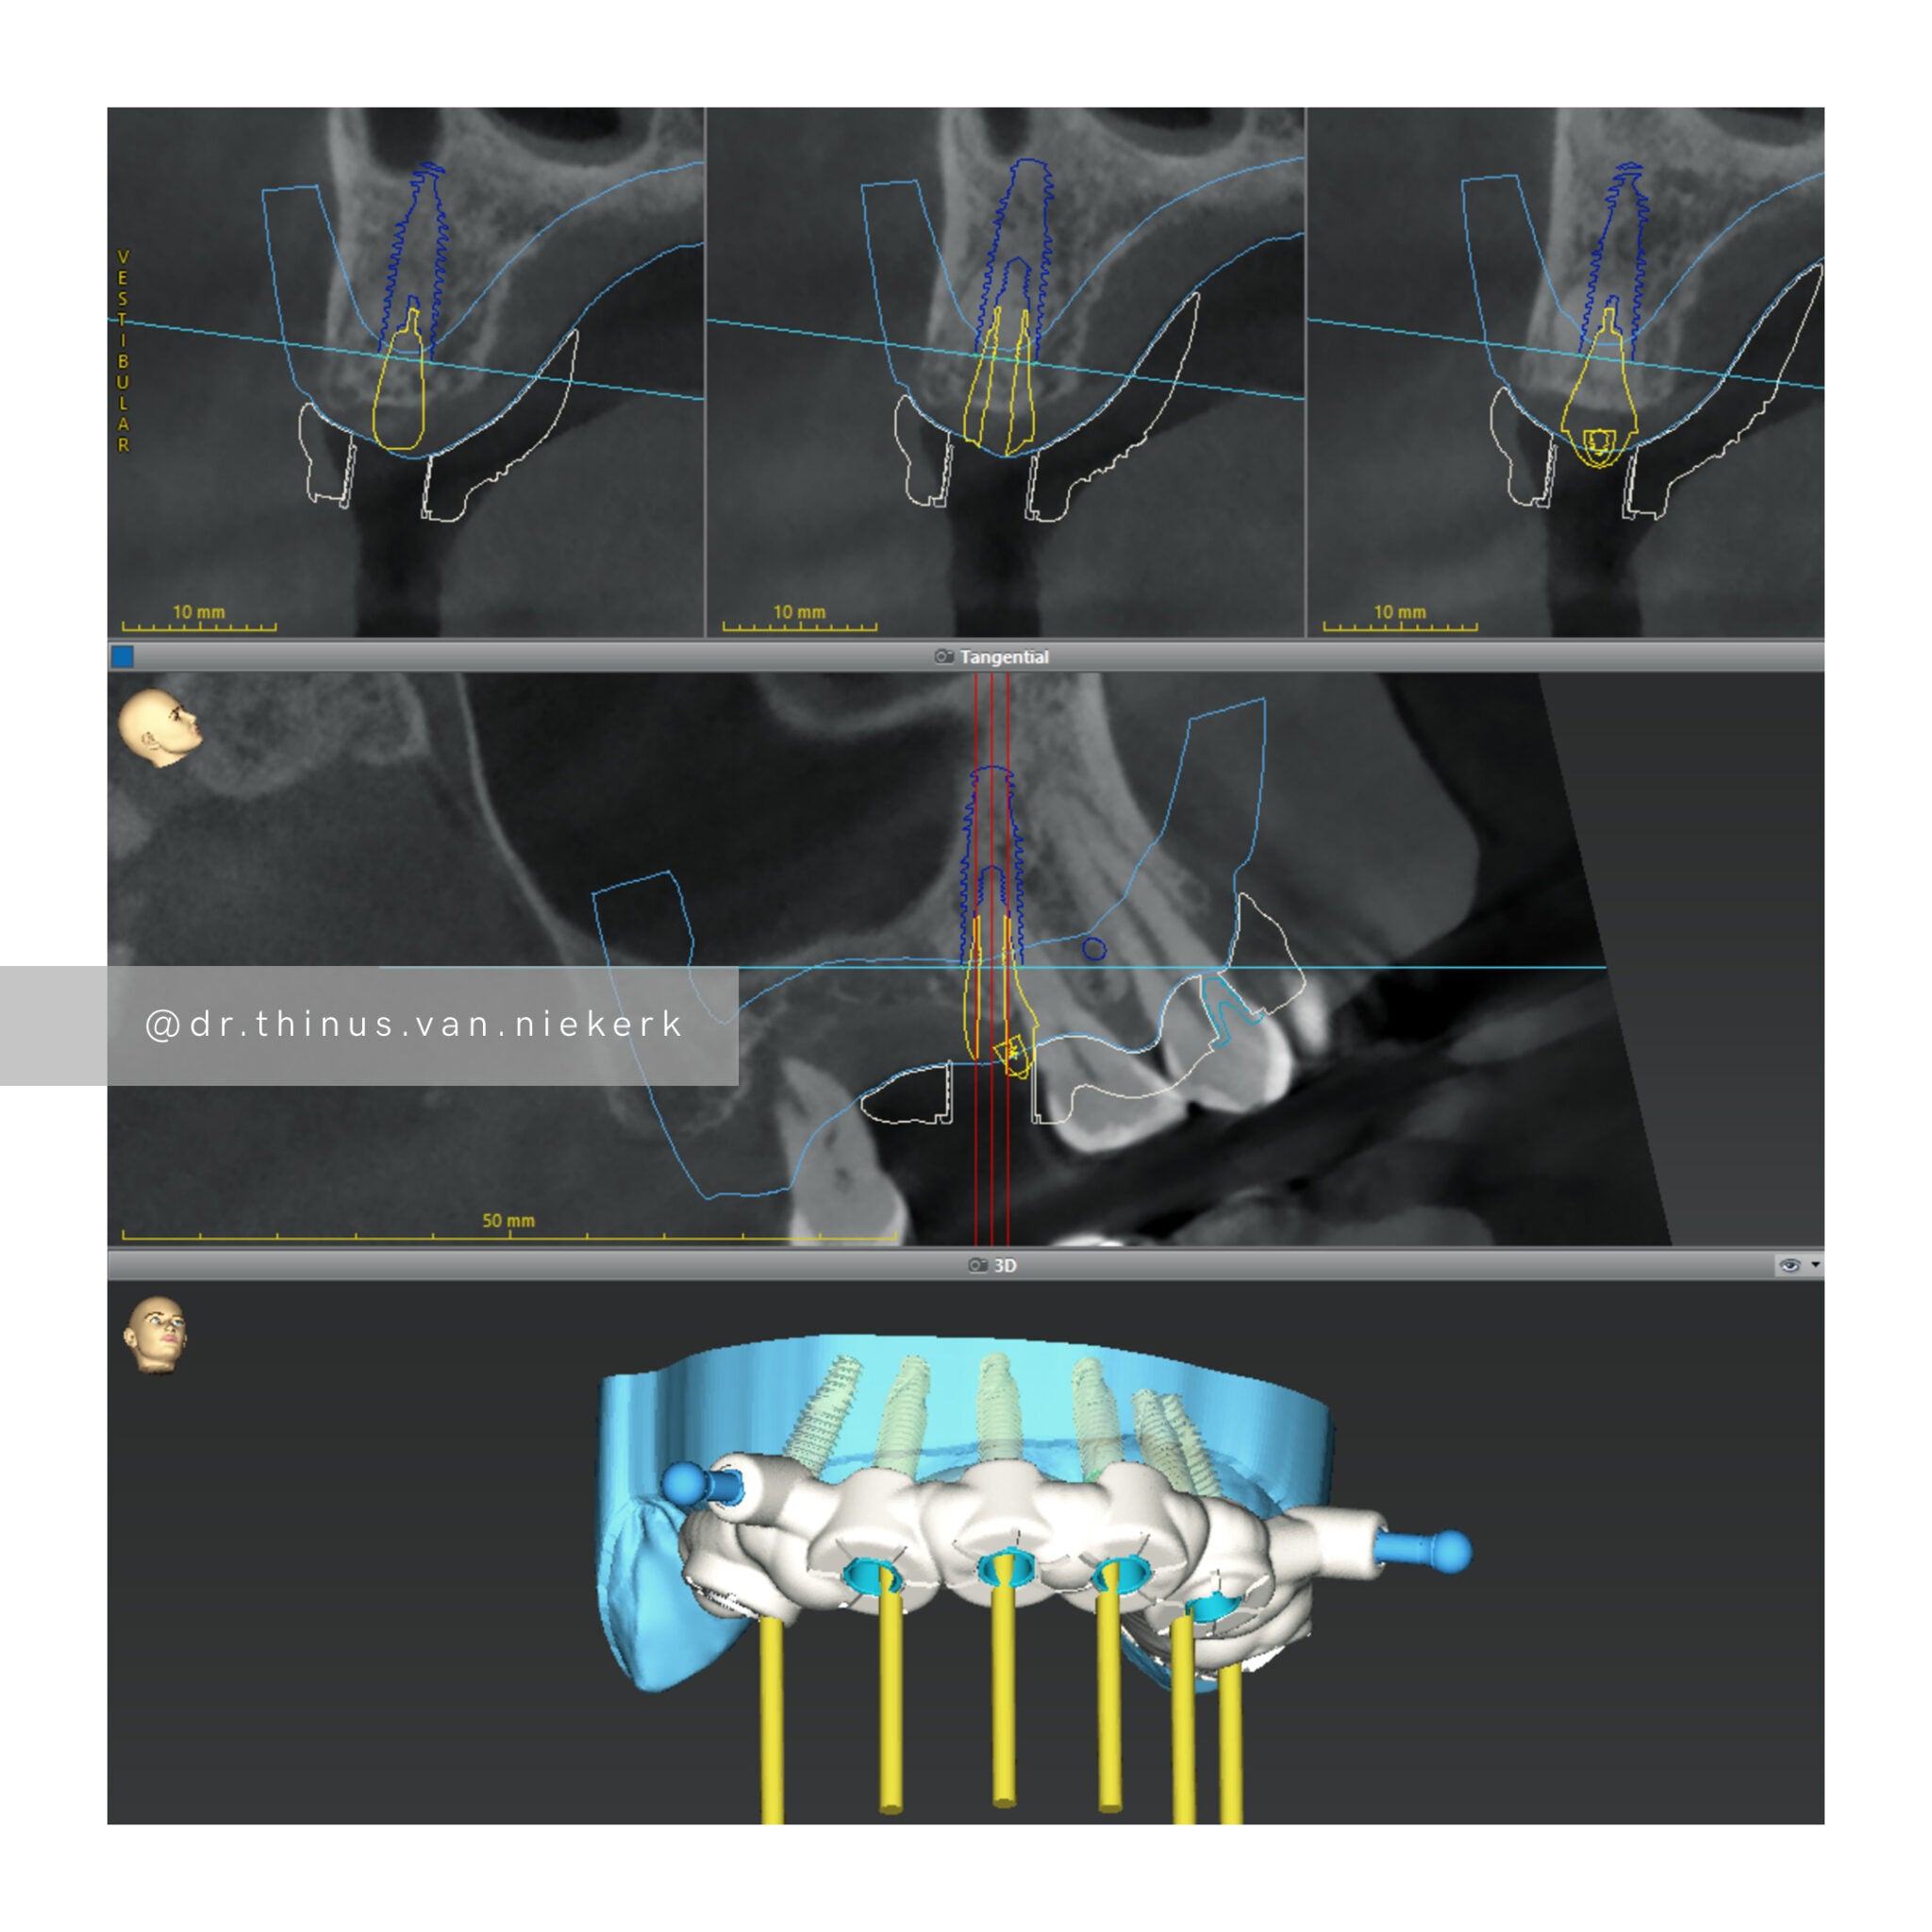

TREATMENT OBJECTIVE

Our aim was to remove all elements of infection and disease and to restore function as quickly as possible. The complete case was digitally planned prior to the day of surgery. Six fully-guided implants were placed during a two-hour morning surgery. An immediate implant-supported prosthesis was delivered on the same day.

COMMENTS

This case demonstrated the power and effectiveness of digital implant-surgery planning and CAD design software.